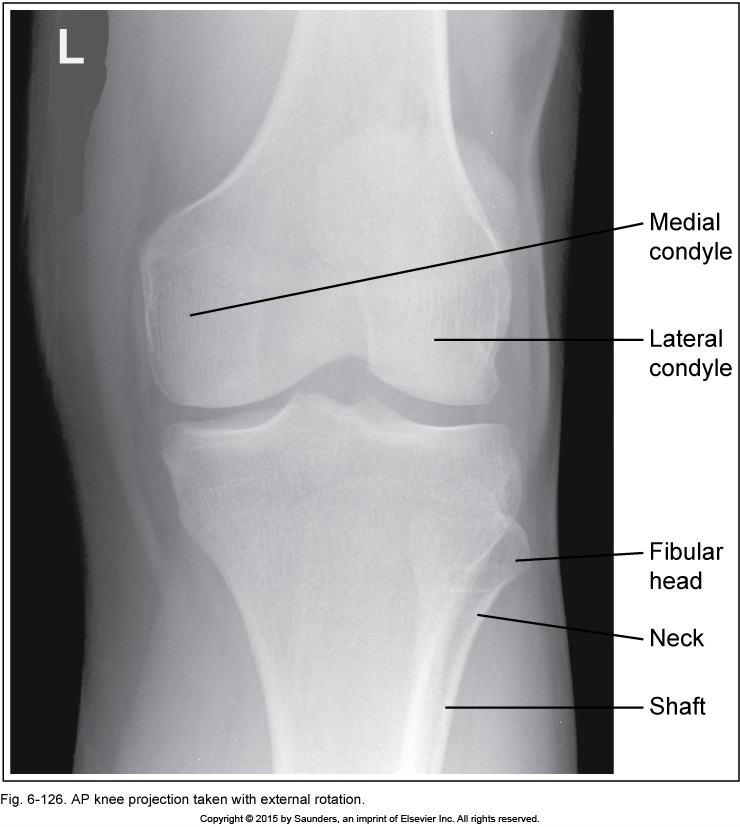

AP knee

external rotation

patella out of place

fibular head superimposing tibia